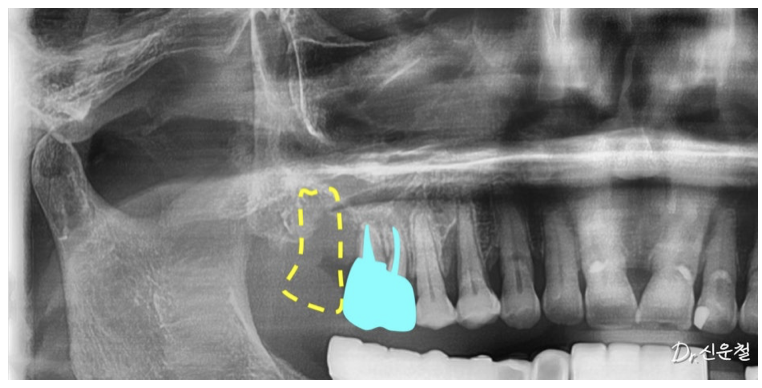

치료 계획을 세우면서

남아 있는 어금니의 상태도 확인했습니다.

촬영일 : 250825

겉으로 보기에는

두 치아 모두 발치가 필요해 보였지만

자세히 검사해 보니 상황이 조금 달랐습니다.

한 치아는 염증이 넓게 퍼져

발치가 더 안전한 상태였고

다른 치아는

신경치료를 통해 충분히 사용할 수 있는 상태였습니다.

그래서 두 치아를 모두 발치하는 대신

한 치아는 발치

한 치아는 신경치료

이렇게 치료 방향을 나누었습니다.